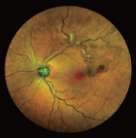

FFA是20世紀(jì)60年代發(fā)展的一項技術(shù)。1961年Navotny 和Alvis首次成功地用膠片記錄到熒光素流經(jīng)視網(wǎng)膜和脈絡(luò)膜血管的動態(tài)過程,開創(chuàng)了眼底熒光血管造影的臨床應(yīng)用時代。如今,F(xiàn)FA主要用于觀察視網(wǎng)膜血管及其血液循環(huán)狀態(tài),高清晰攝像技術(shù)能動態(tài)捕捉視網(wǎng)膜毛細(xì)血管的循環(huán)狀態(tài),間斷或連續(xù)采集可形成視網(wǎng)膜靜態(tài)的黑白圖像或動態(tài)圖像,在診斷中敏感性強,確診率高,能發(fā)現(xiàn)檢眼鏡或眼底照相下不易發(fā)現(xiàn)的視網(wǎng)膜深層微血管瘤,是判斷視網(wǎng)膜病變的“金標(biāo)準(zhǔn)”

FFA影像